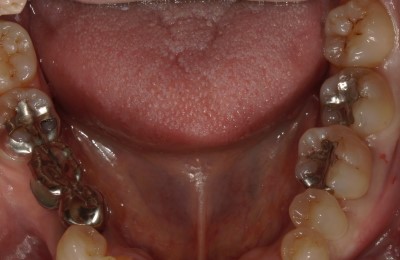

CASE03ダイレクトボンディング

Before

-

After

| 主訴 | できるだけ歯を削らずに銀歯を白くしたい。 |

|---|---|

| 治療方法 | 銀歯を除去した後、ダイレクトボンディング法によりコンポジットレジンを用いて修復した。 |

| 治療期間 | 1回 |

| リスク | 長年使用することによる着色。咬合圧が強い場合破折することがある。 |

| 費用 | 55,000円×2(税込み) |